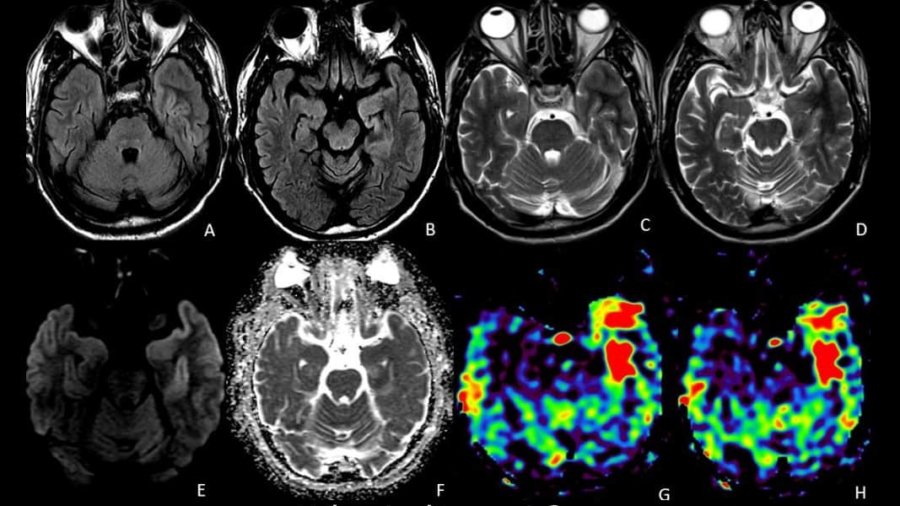

A 71 year old male presented with 1-year history of ocular symptoms (diplopia, proptosis, episcleral congestion).

A 30 year old female with headache. What is the diagnosis?

An elderly male, known diabetic with one episode of seizure. What is the diagnosis?